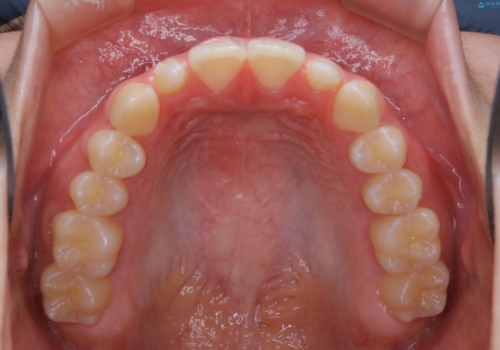

前歯や小臼歯では、生えてくる歯が小さく審美的に影響が出る場合があります。このような歯を矮小歯(わいしょうし)と言います。

今回のケースでは、歯が小さいだけでなく傾斜もしていたため補綴治療時に歯を削ることで神経の症状が出る可能性がありました。そのため、事前に部分矯正を行い歯軸の改善を行っておくことで、歯髄を温存することができました。

奥歯の噛み合わせに問題がなく、矯正で必要となる歯牙の移動量が軽微である場合に部分矯正が適用になる場合があります。

変える必要のない部分には手を出さず、必要な部分に最小限の処置を施すことで費用や期間の削減をすることが可能となります。